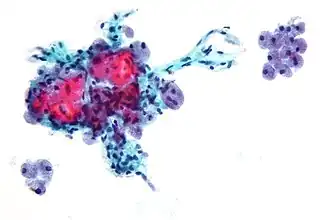

Клетки Гюртле (Hürthle cells) — это большие клетки, часто ассоциированные с фолликулярным раком щитовидной железы. При микроскопическом исследовании окрашенных культур имеют розовый цвет. Клетки названы в честь немецкого патолога Карла Гюртле (1860—1945)[1].